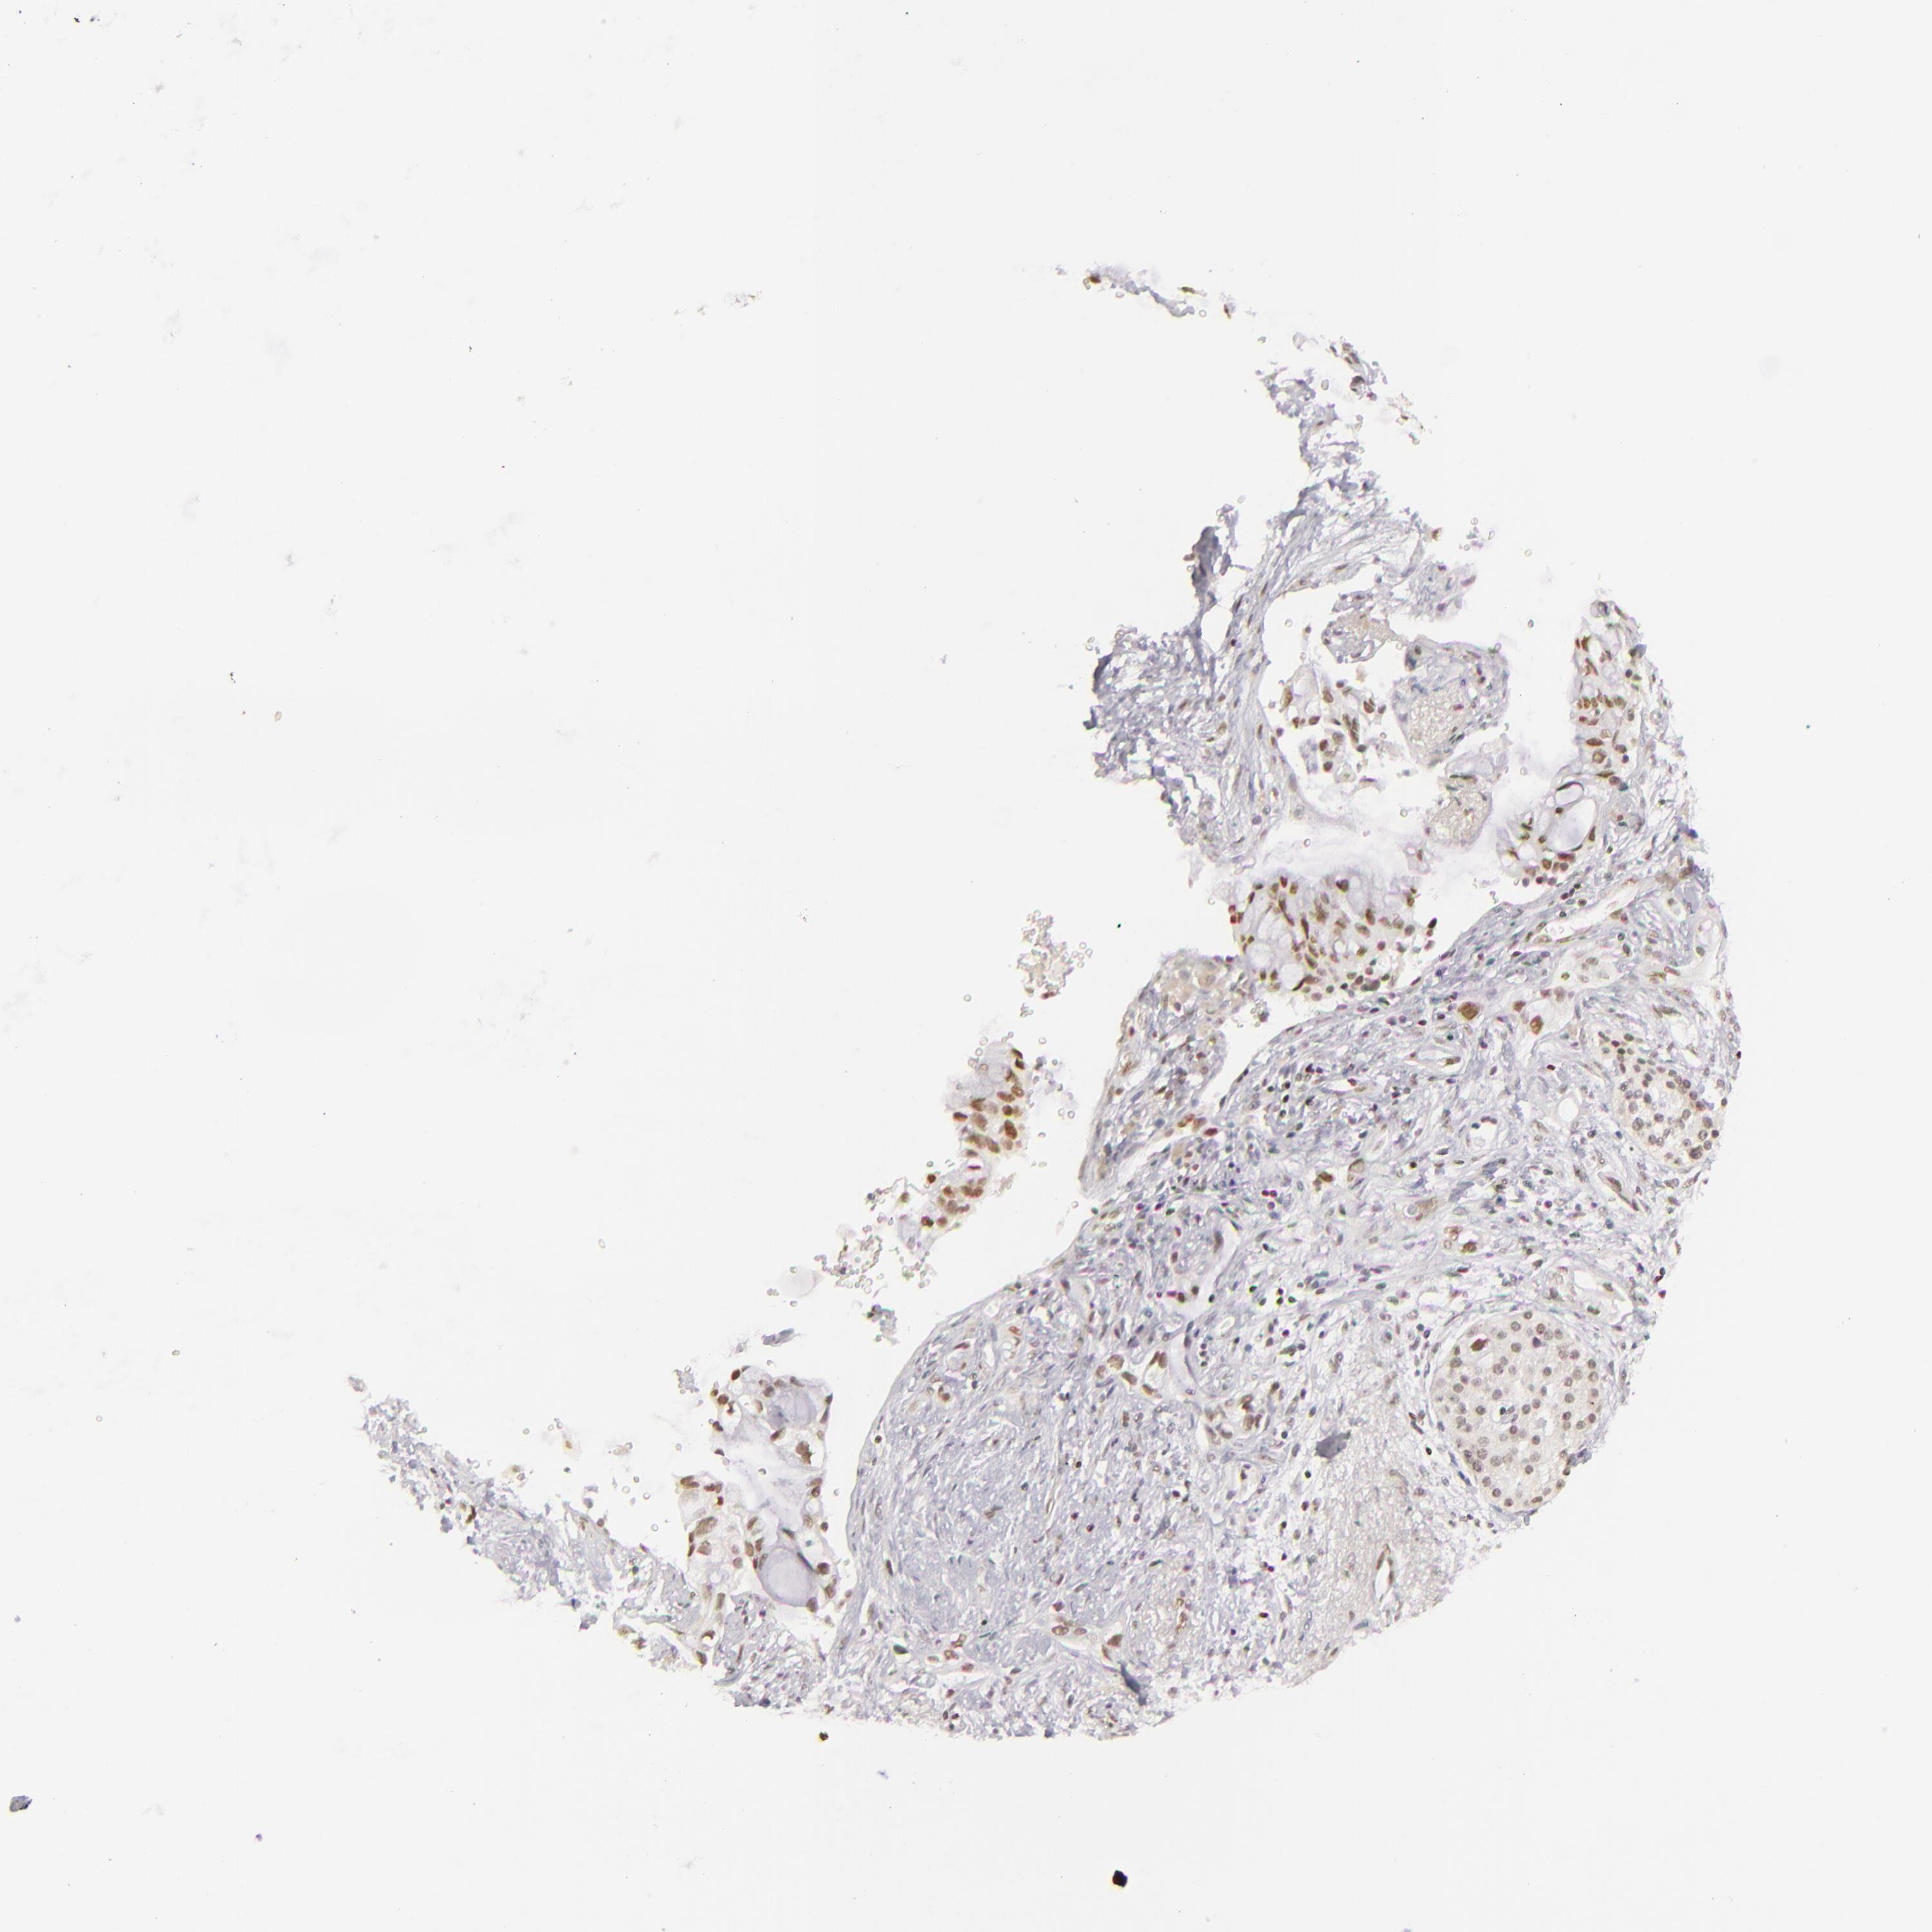

PANCREATIC CANCER - Protein expressioni

A mouse-over function shows sample information and annotation data. Click on an image to view it in a full screen mode. Samples can be filtered based on level of antibody staining by selecting one or several of the following categories: high, medium, low and not detected. The assay and annotation is described here.

Note that samples used for immunohistochemistry by the Human Protein Atlas do not correspond to samples in the TCGA dataset.

Antibody stainingi

Antibody staining in the annotated cell types in the current human tissue is reported as not detected, low, medium, or high, based on conventional immunohistochemistry profiling in selected tissues. This score is based on the combination of the staining intensity and fraction of stained cells.

Each image is clickable and will lead to virtual microscopy that enables deeper exploration of all samples and also displays staining intensity scores, fraction scores and subcellular localization as well as patient and tissue information for each sample.

Antibody HPA008736

Antibody CAB002224

Antibody CAB025546

Staining

High

Medium

Low

Not detected

Intensity

Strong

Moderate

Weak

Negative

Quantity

>75%

75%-25%

<25%

None

Location

Nuclear

Cytoplasmic/membranous

Cytoplasmic/membranous,nuclear

Adenocarcinoma, NOS

Adenocarcinoma, metastatic, NOS